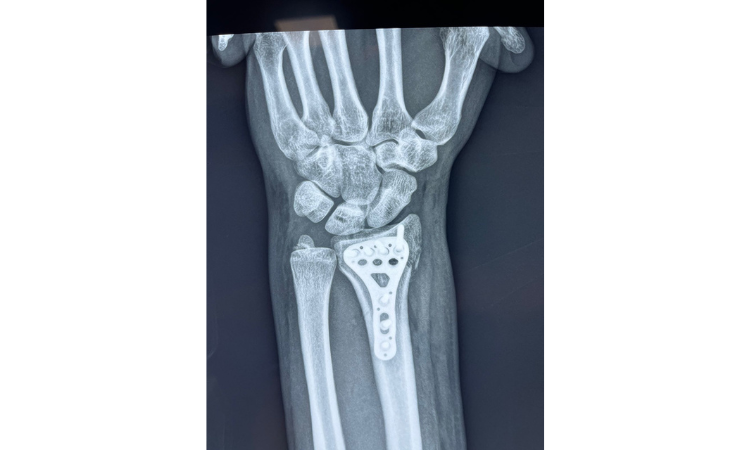

1. Radio: El radio es el hueso más grande del antebrazo y se encuentra en el lado lateral de la muñeca. Las fracturas del extremo distal del radio mas conocidas son las descritas como fractura de Colles o fractura de Smith segun la dirección del desplazamiento del fragmento. Estas fracturas pueden ocurrir debido a una caída sobre la mano extendida.

2. Cúbito: El cúbito es el otro hueso del antebrazo y se ubica en el lado medial de la muñeca. Las fracturas del cúbito pueden ocurrir en combinación con las fracturas del radio.

El diagnóstico se realiza mediante una evaluación clínica y radiografías. El tratamiento básico para las fracturas de muñeca implica la inmovilización adecuada del área afectada. Esto se logra generalmente mediante la colocación de un yeso o una férula para mantener los huesos en su lugar mientras sanan. En algunos casos, puede ser necesario realizar cirugía para realinear los fragmentos óseos.